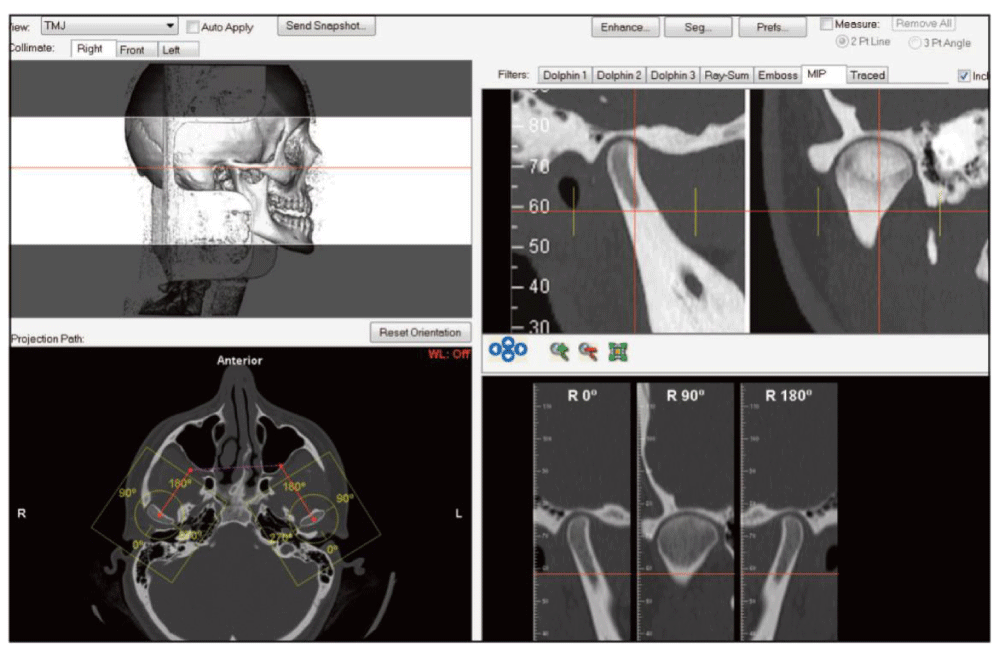

Nineteen consecutive patients previously treated for their temporomandibular pathologies were studied by CBCT images and Dolphin Imaging Software 11.7, permitting the Second Phase of the treatment [Figure 1,2].

Figure 2: Screen printing of the software image used as a planning and diagnostic tool, in which images similar to those used to conduct research, were observed.